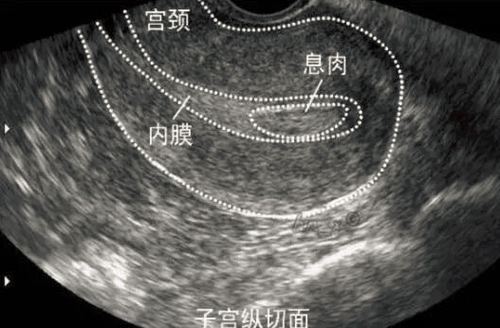

子宫息肉是生在在子宫内膜局部位置的一种情况,子宫息肉侵害了女性的身体健康,大多数情况下,子宫息肉是属于良性的,它是过度生长而形成的赘生物,那么女性对于这种情况也要及时采取措施来处理,不过,未婚女性子宫息肉怎么办?